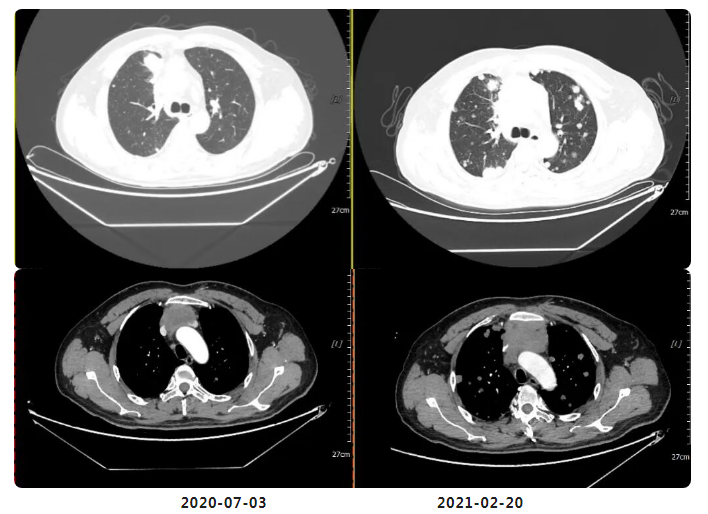

治疗相关影像资料:

与2020年7月3日片对比:两肺多发异常结节较前明显增多、增大(原约3.2×2.1,现约3.9×3.0cm);纵膈前间隙、纵隔内及两肺门多发增大淋巴结较前部分增大(原约5.2×3.4,现约6.7×4.0cm)并胸骨受累(新出),邻近上腔静脉及左头臂静脉受累较前加重。